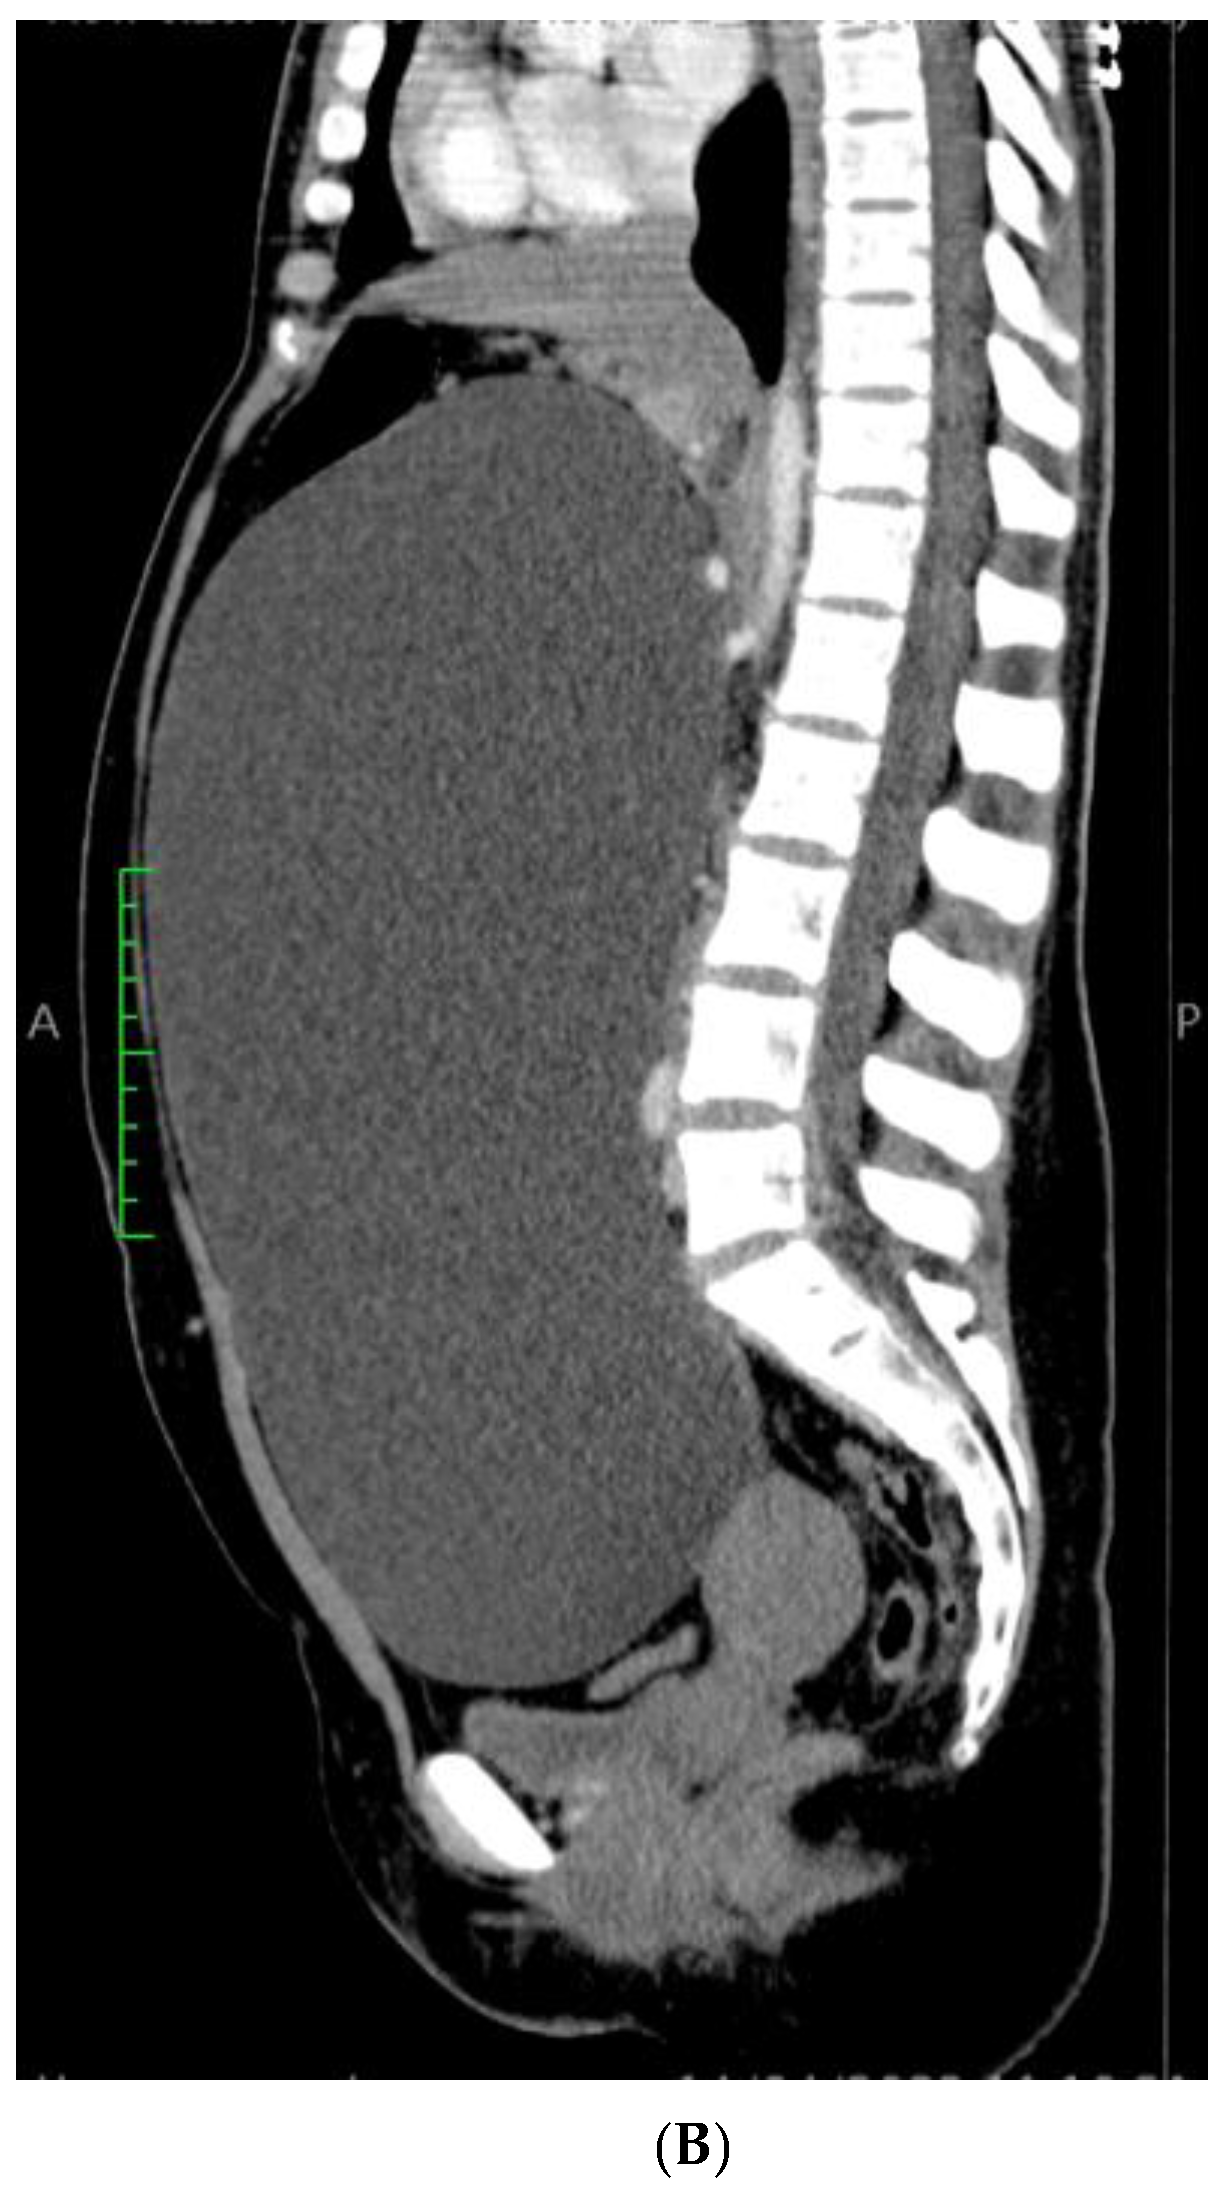

The cyst had a morphological connection with the fallopian tube (Figure 6), which presented a mucosa lined by a simple columnar epithelium with focal stratification.

Figure 6. Paratubal cyst, lined by a simple, flat, cuboidal to columnar epithelium, in morphological continuity with the fallopian tube wall (HE ×10).